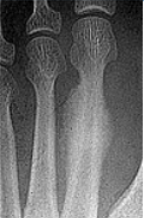

Describe the alignment of metatarsal 2 | There is no angulation nor displacement of the distal segment relative to the proximal segment. |

Describe the alignment of metatarsal 3 | The distal segment is displaced laterally (50% apposition) and angulated medially. |

Describe the alignment of metatarsal 4 | The distal segment is displaced laterally (75% apposition) but there is no apparent angulation. |

Describe the tubulation of the metatarsals | Metatarsals are overtubulated - decreased girth. |

Describe the tubulation of the metatarsals | Metatarsals are undertubulated - increased girth. |